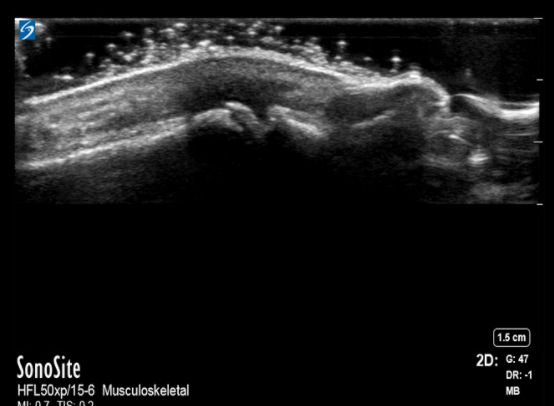

Hand MCP Joint with Inflammation Image